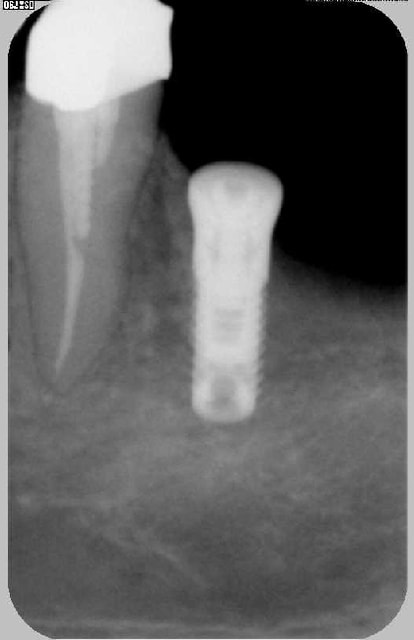

j'avais interprété les photos dans l'ordre suivant:

-implant à 3-4 mois

- implant + couronne quelques mois après la mise en charge

alors qu'en fait c'est l'implant le jour de la pose et la couronne le jour de sa mise en place .

je pensais donc, que la destruction osseuse était vraisemblablement dûe à un problème occlusal alors qu'en fait, en remettant les photos dans l'ordre, on peut rejeter cette hypothèse car l'os s'est reformé grâce à la persistance d'une trame collagénique et à la stimulation mécanique (avec élimination maximale bactérienne dans la zone)

ci-dessous les photos dans l'ordre où je les avais classé: